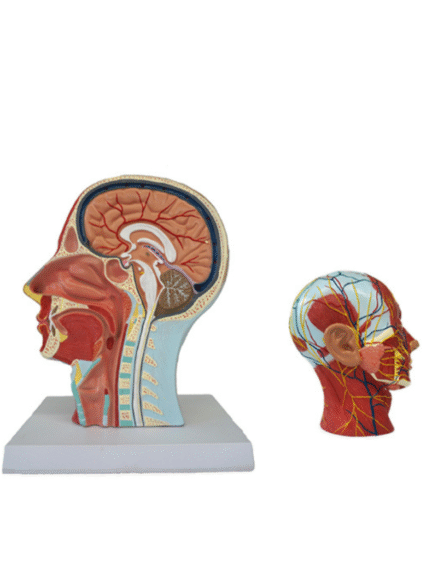

ATL-131 HALF MUSCULAR HEAD WITH VESSEL SOFT

Life size model shows the right half of the human head and neck, sectioned along the sgittal plane. A superficial dissection exposes the facial muscles, the superficial blood vessels and nerve branches of the face and scalp, the parotid and submandibular glands. A median dissection expose the brain with its internal structure, tha pharynx and upper respiratiry tract, a section of the cervical vertebrae.